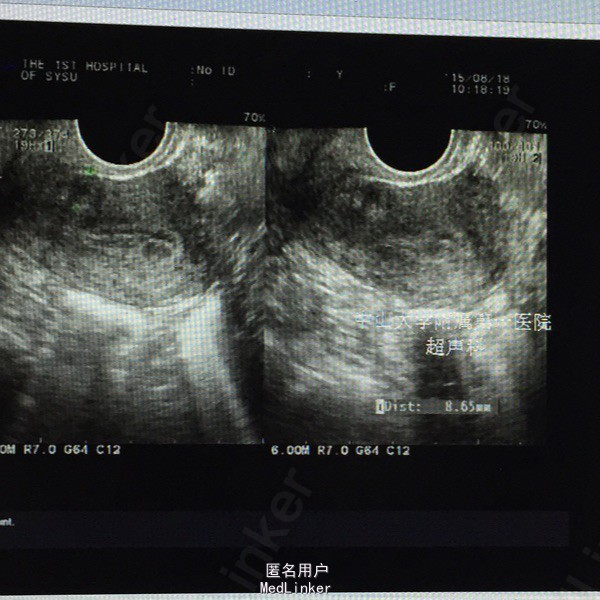

妇查:无异常。 辅查:2015-05-28外院行输卵管三维超声造影检查,结果提示“左侧输卵管通而不畅,右侧输卵管近段阻塞”。 2015-8月我院妇科B超示: 子宫内膜厚径9mm, 肌层回声欠均,子宫前壁低回声区9mm×7mm,考虑小型子宫肌瘤。